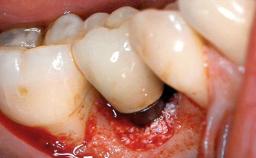

In 2004, the patient, a smoker, began dental treatment at the ACTA graduate clinic. She was a TV producer exposed to a lot of stress in her job and had a sick husband. Her maxillary teeth had been extracted, as had the mandibular canines, premolars, and molars, with the exception of tooth 34. She received a complete maxillary denture and a mandibular skeleton denture. In October 2007, her maxilla was augmented by an oral and maxillofacial surgeon; in March 2008, implants (Biomet 3i, Palm Beach, Florida, USA) were inserted at that same clinic. In 2008, the patient was presented at the Department of Oral Implantology and Prosthetic Dentistry to request restorations for her implants. An implant-supported overdenture was planned. She also asked if we could restore her occlusion with fixed prosthetics.